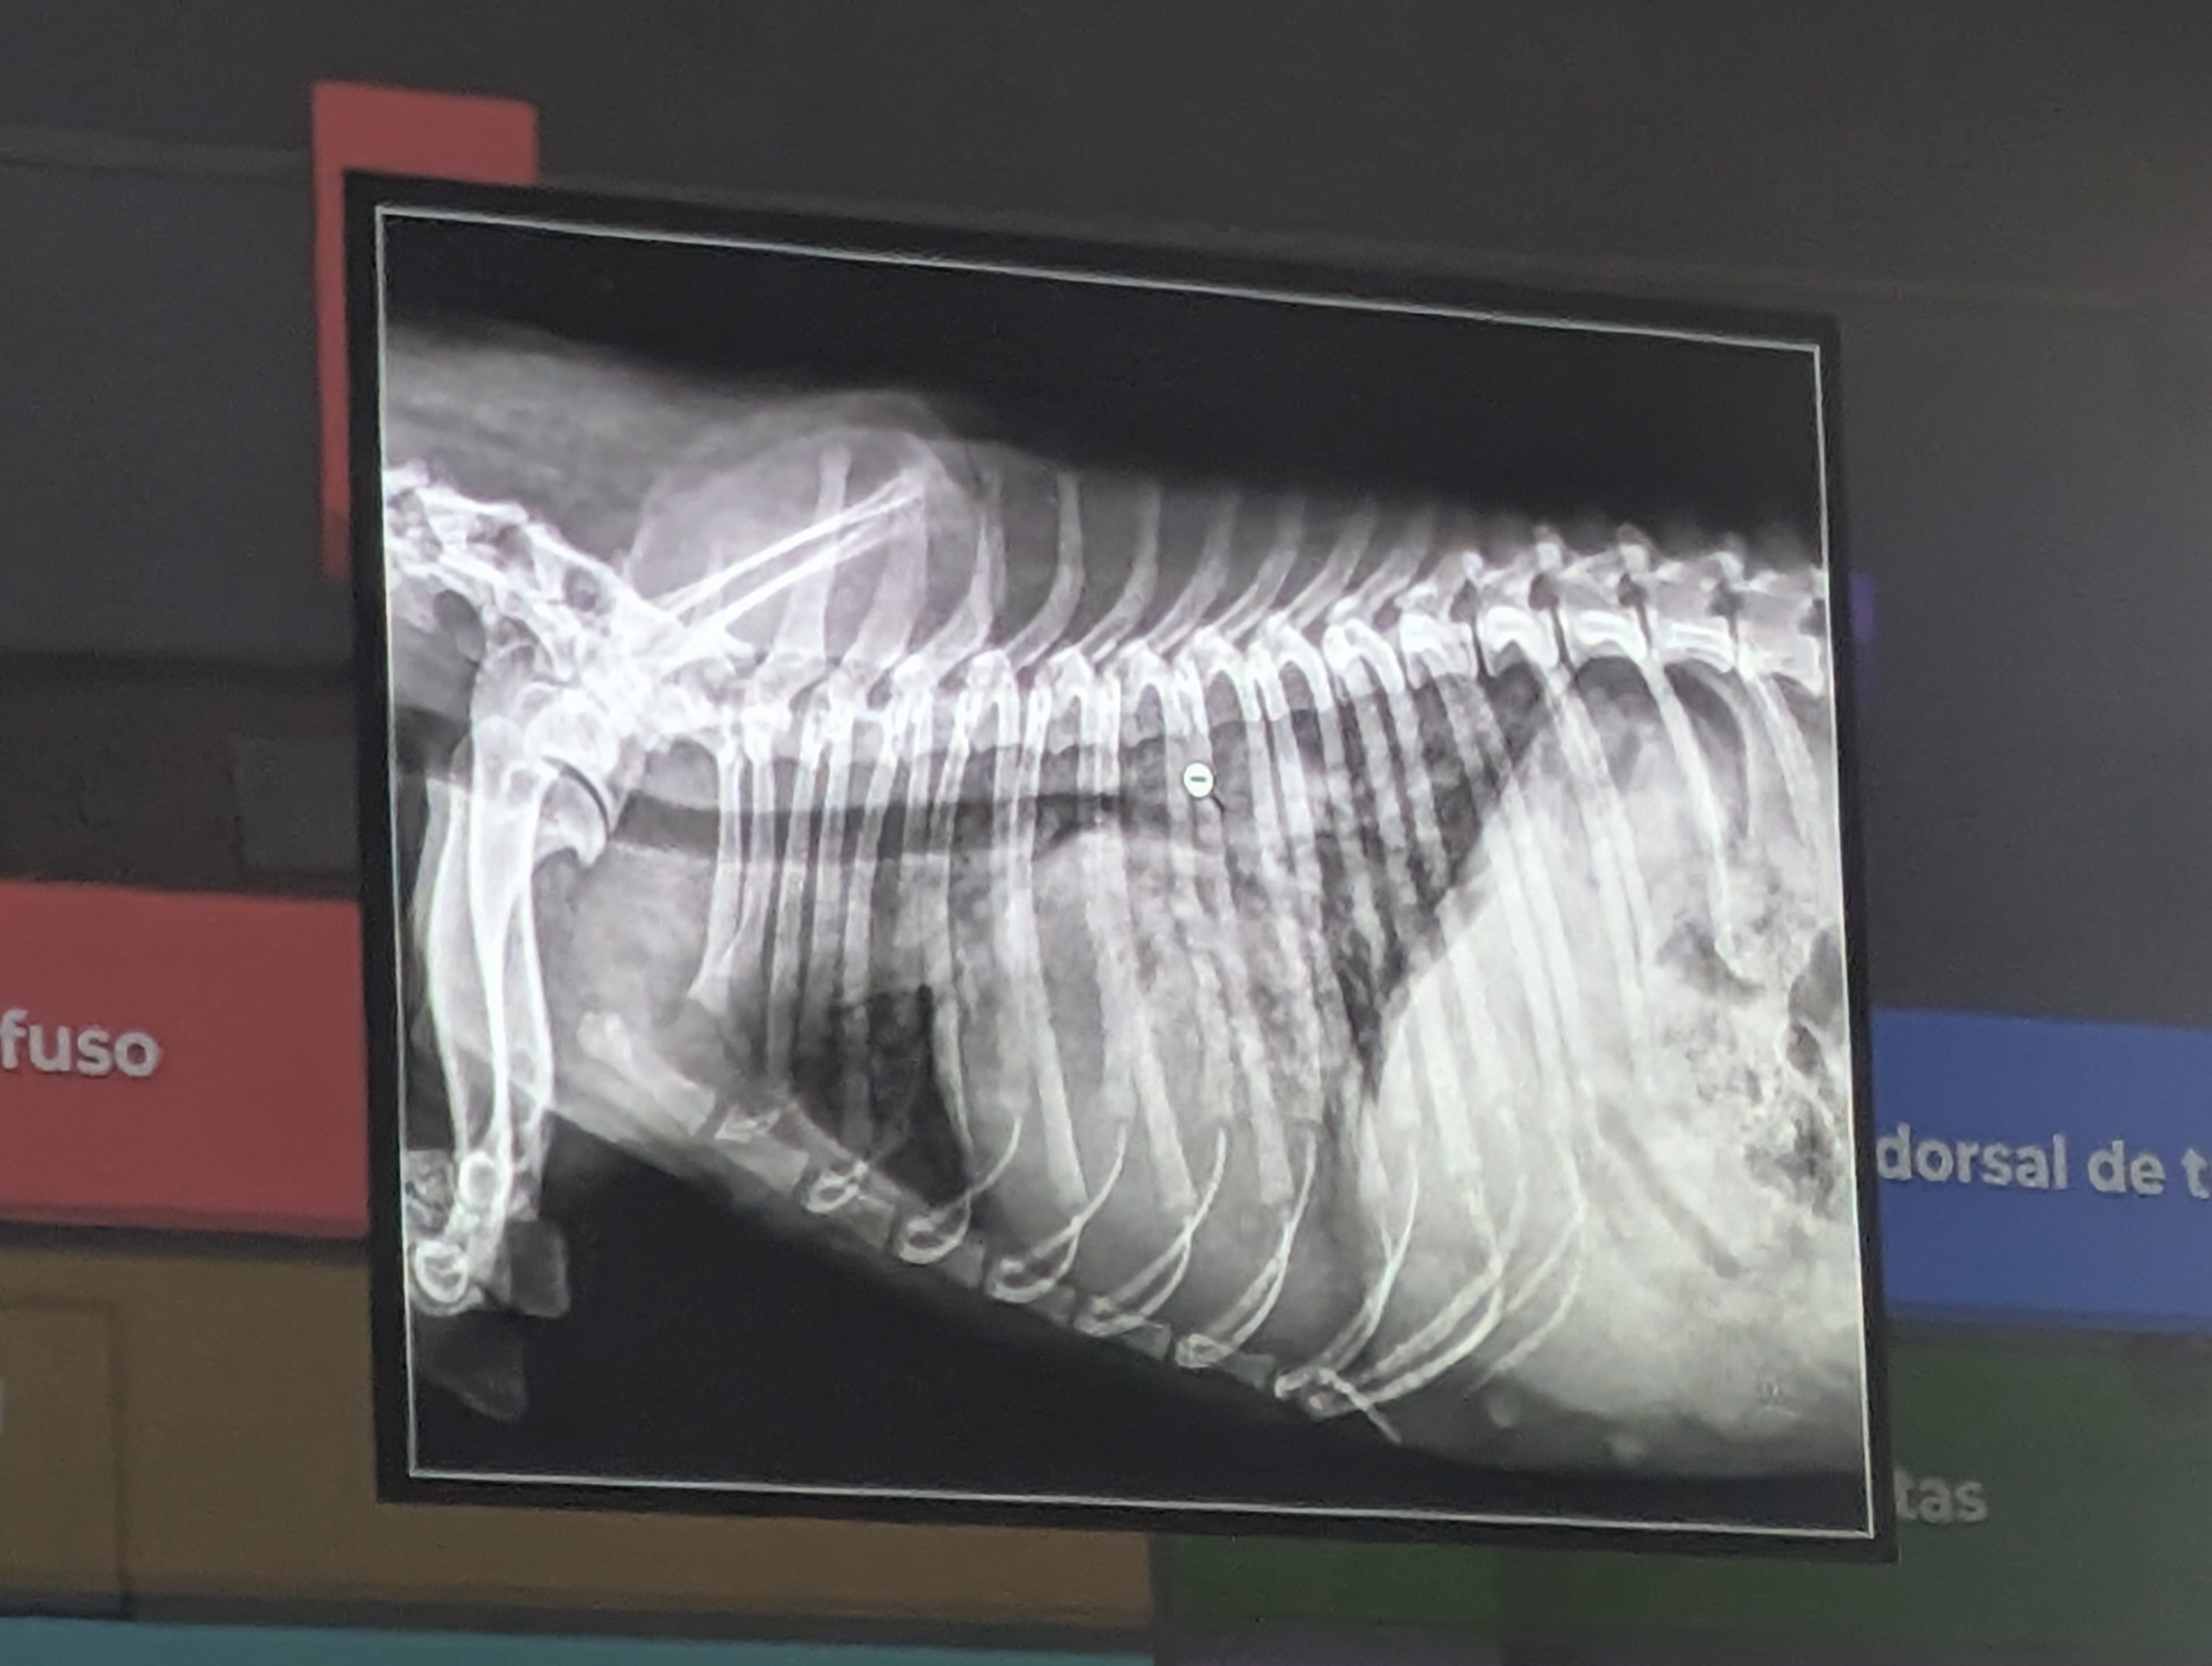

1) Una respuesta correcta

- Patron Intersticial (Difusa, no estructurado, se ve la vena cava y aun hay negros, por eso no es alveolar) IMPORTANTE Patrones bronquiales no suelen entrar porque se ven mal de los donuts